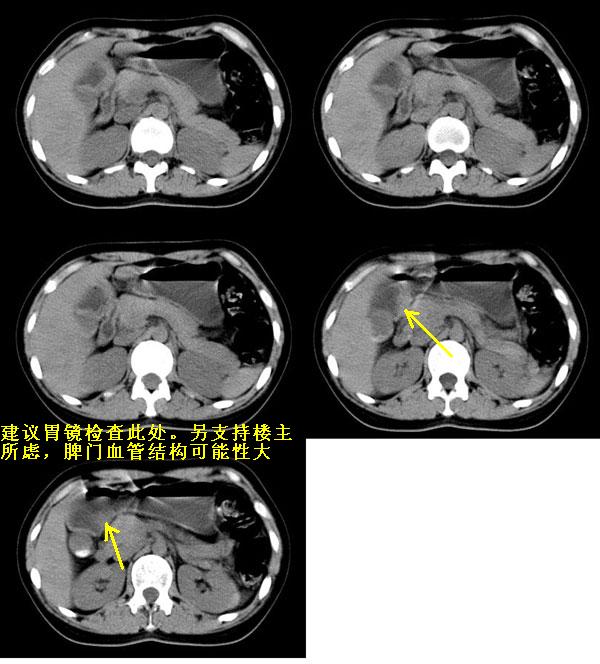

以下是引用guzhongliangddd在2006-11-9 17:55:00的发言:[br]请重点讨论图中箭头所示{脾门部,我首先考虑的是1:血管结构2:胰尾组织??)[br][br][本贴已被 guzhongliangddd 于 2006-11-9 18:01:50 修改过]

以下是引用西北偏北在2006-11-9 20:15:00的发言:[br]箭头所指结构边缘不光整,不支持副脾,考虑胰尾容积层面或血管,做个增强吧.

以下是引用无泪之城在2006-11-9 20:01:00的发言:[br]考虑副脾,建议增强,请把增强片传上来